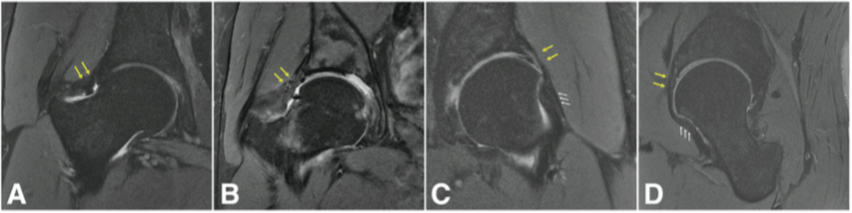

近年来我所已开展针对成人髋关节发育不良的保髋治疗。目前髋关节组已开展髋臼周围截骨术、股骨去旋转截骨术近五十例,包括专业运动员3例,近期随访效果满意。同时,髋关节组在国内率先开展了髋关节镜联合髋臼周围截骨术,首先利用髋关节镜下将关节内的盂唇及软骨损伤进行修复,然后通过髋臼周围截骨手术改善患者的髋臼覆盖情况。本手术方式可以更好地提高患者的手术疗效。这丰富了我所髋关节疾病的治疗手段,极大推动了髋关节专科的学科发展。